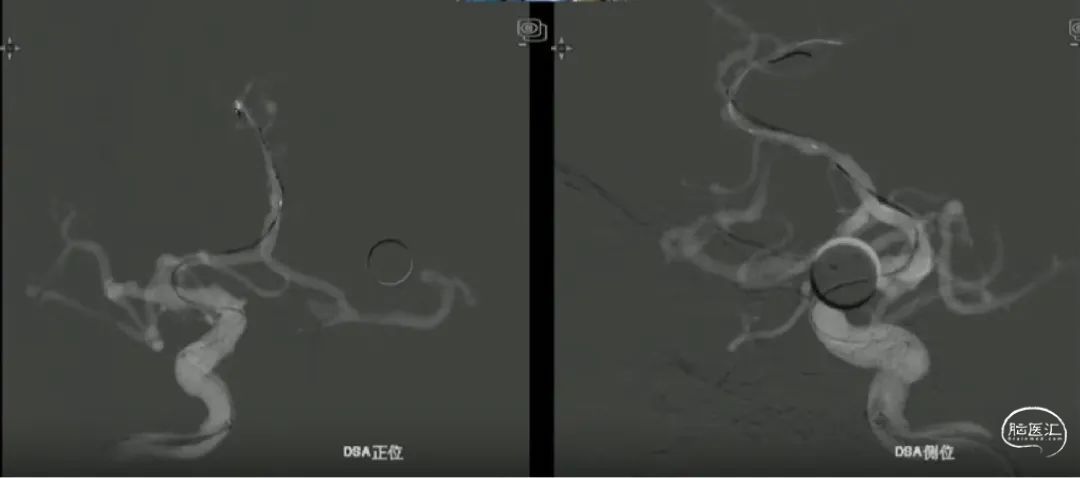

术前影像

· 患者三型弓,奇大脑前A3段动脉瘤,形态极不规则,血管入路极其迂曲

· 从大脑前动脉瘤起始段,有广泛伴有动脉粥样硬化的斑块

· 病变远端处于奇大脑前动脉双分叉位置,远端支架可着陆的空间较短,远端血管较细,且伴随斑块

术前测量

远端锚定点:1.5mm

瘤颈远端:1.53mm

瘤颈近段:2.4mm

动脉瘤瘤体直径:4.40mm